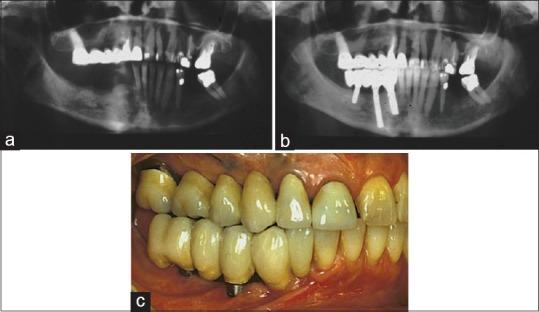

This article reviews relevant dental literature to answer some frequent questions related to evidence-based implantology. There are hundreds of implant systems on the market, but the majority lack clinical documentation. Recommended number of implants for full-arch fixed prostheses is four or five in the mandible but at least six in the maxilla. Less expensive implant-retained overdentures make implant treatment available to a greater portion of edentulous subjects. Mandibular overdentures on two implants, and even one implant, have shown excellent long-term outcomes. In the maxilla, less than four implants are not recommended for good results. Single implant restorations have good prognosis, but placement of the implant should be postponed until adulthood. Osseointegrated implants have revolutionized clinical dentistry. However, in a global perspective, implants make up only a small part of all prosthodontic treatment. Knowledge and skill in conventional prosthodontics must be maintained as it will remain the most common part of the specialty.

本文回顾了相关牙科文献,以回答一些与循证种植学相关的常见问题。市场上有数百种植体系统,但大多数缺乏临床文献记录。全牙弓固定修复体推荐的种植体数量在下颌为4或5颗,但在上颌至少为6颗。价格较低的种植体支持式覆盖义齿使更多无牙患者能够接受种植治疗。两颗种植体甚至一颗种植体支持的下颌覆盖义齿已显示出优异的长期效果。在上颌,为获得良好效果,不建议使用少于4颗种植体。单颗种植体修复预后良好,但种植体植入应推迟至成年期。骨结合种植体彻底改变了临床牙科。然而,从全球角度来看,种植体在所有口腔修复治疗中只占一小部分。必须保持传统口腔修复学的知识和技能,因为它仍将是该专业最常见的部分。